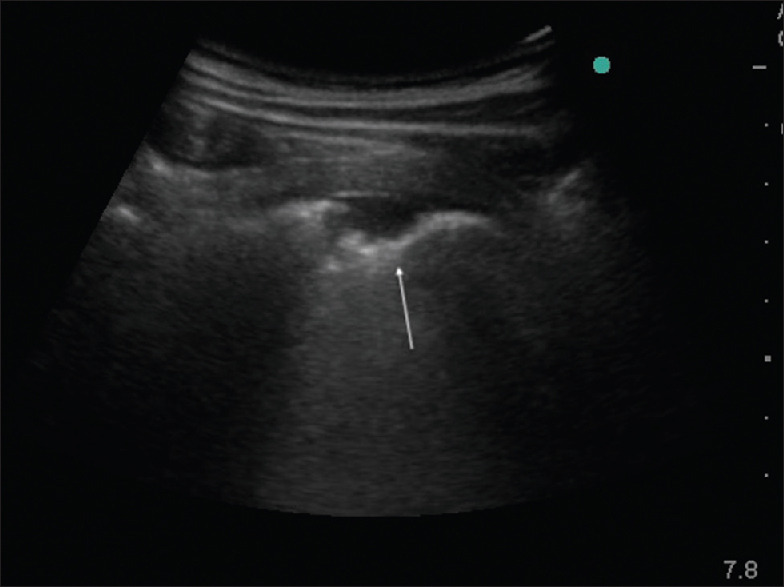

Results: Ninety-six subjects with 64 microbiologically confirmed TB and 32 lobar pneumonia patients were included. The study subjects' mean age was 46.78 ± 15.75 years and the majority were males (n = 62; 64.6%). LUS showed focal interstitial pattern, cavity, and irregular pleura in TB patients which were significantly different (P ≤ 0.001) from the findings of air bronchogram and/or shred sign seen in patients with lobar pneumonia. The overall sensitivity of LUS compared to X-ray, to identify abnormalities in TB and lobar pneumonia patients, was 88.6%. The LUS and CXR findings were concordant in 93.75% of TB patients and 90.6%) of lobar pneumonia patients. Additional USG abnormalities other than that seen on CXR were demonstrated in 13 (20.3%) TB patients.

Conclusion: LUS is a valuable tool to detect TB and lobar pneumonia and can discriminate between the two conditions. LUS performance was on par with CXR in the detection of abnormalities. The lack of radiation exposure and portability of LUS makes it an attractive tool for bedside use as well as in field conditions where radiography may not be readily available.

Abstract Image